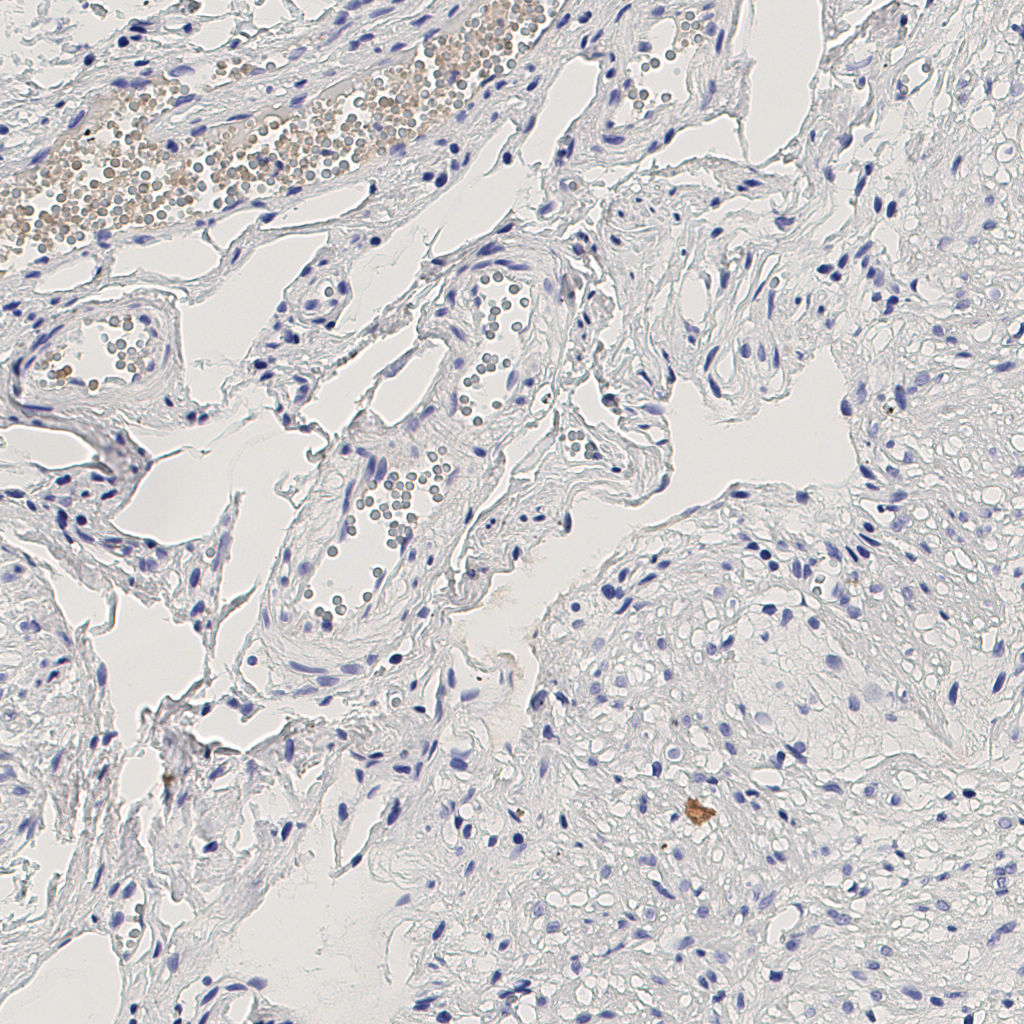

7.85%

Ki67 指数

阴 1104

阳 94

标记后

标记前